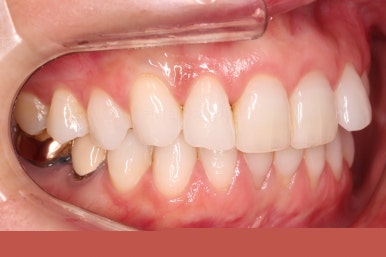

윗니에만 장치를 부착하고 부분교정을 시작했습니다.

환자분이 연산동부분교정 선택하신 장치는 엠파워 클리어라고 하는 자가결찰 세라믹 장치입니다.

장치 부착한 모습 참고해 주시고요.

적절하게 치간삭제를 일부 동반하여 빠른 시일 내에 가지런하게 해드리고 마무리를 했습니다.